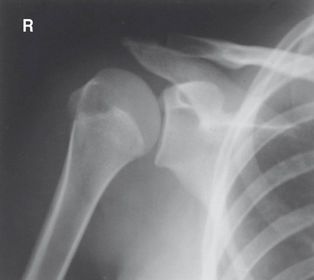

Which projections/positions are these? (top->bottom) TOP: Scapular Y-View _________________________ BOTTOM: AP External Rotation (greater tubercle in profile)